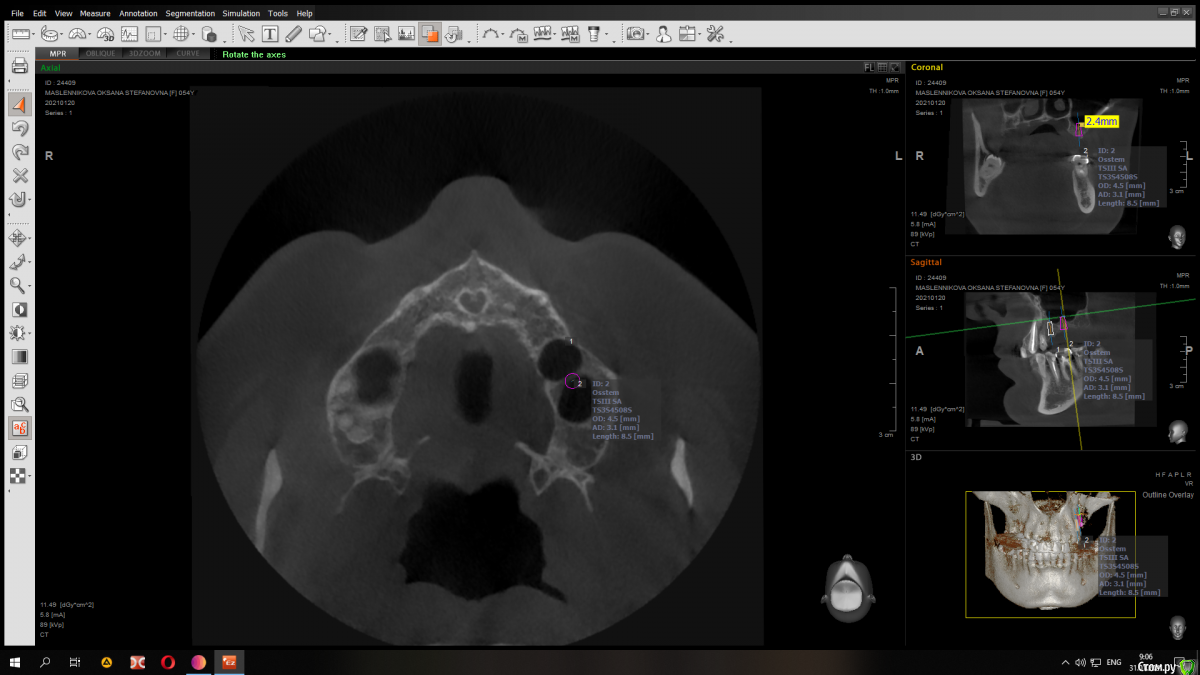

Raystom Опубликовано 31 января, 2021 Автор Поделиться Опубликовано 31 января, 2021 Конечно) Вот вариант с 8.5 мм имплантатом Ссылка на комментарий

red_butler Опубликовано 31 января, 2021 Поделиться Опубликовано 31 января, 2021 Имхо замеры сделаны не правильно, но не вижу проблем. Если нет остеотомов, то закрытый синуслифт можно выполнить имплантом 1 Ссылка на комментарий

Raystom Опубликовано 31 января, 2021 Автор Поделиться Опубликовано 31 января, 2021 Имхо замеры сделаны не правильно, но не вижу проблем. Если нет остеотомов, то закрытый синуслифт можно выполнить имплантом в чем ошибка в замерах? Ссылка на комментарий

red_butler Опубликовано 31 января, 2021 Поделиться Опубликовано 31 января, 2021 в чем ошибка в замерах?замеры используя шаблон импланта Ссылка на комментарий

Fin Опубликовано 2 февраля, 2021 Поделиться Опубликовано 2 февраля, 2021 Коллеги, в данном случае какую длину имплантата Вы посоветовали? Как Вы считаете нормально ли в данном случае брать импл. 8.5 и он будет в гайморовой на 2,5 мм? Или лучше взять покороче? Ссылка на комментарий

red_butler Опубликовано 3 февраля, 2021 Поделиться Опубликовано 3 февраля, 2021 Коллеги, в данном случае какую длину имплантата Вы посоветовали? Как Вы считаете нормально ли в данном случае брать импл. 8.5 и он будет в гайморовой на 2,5 мм? Или лучше взять покороче?8-9 мм Ссылка на комментарий